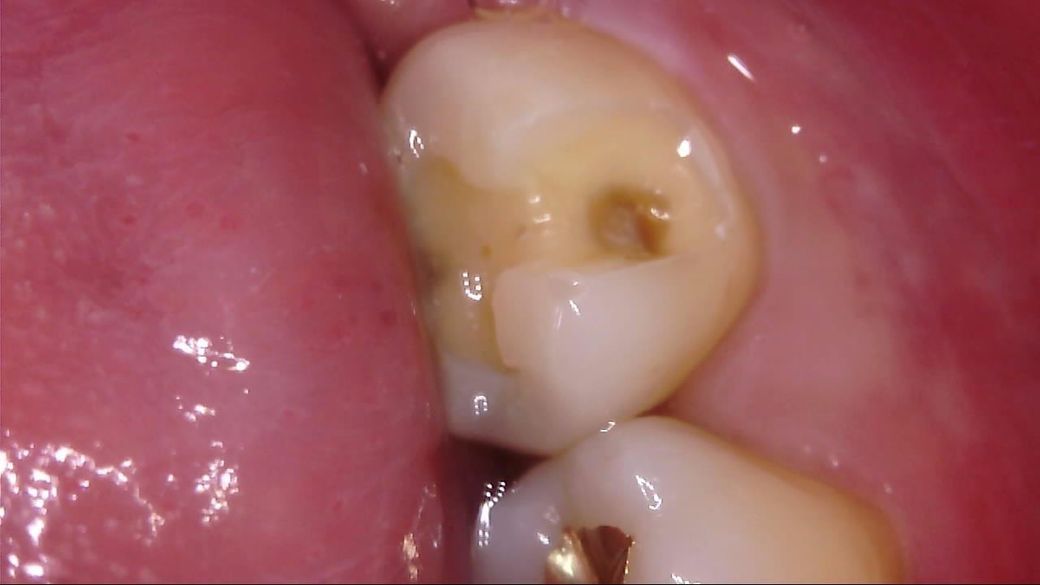

이차 우식이 상당히 깊게 발생하였는데, 치료 과정에서는 아래 사진과 같이 선생님께서 아래와 같이 일부 갈색 부분을 남긴 채 치아 삭제를 마치고 보철을 진행해 주셨습니다.

선생님께서는 "해당 부분은 착색 부위로, 이대로 덮어도 무방하다"라고 말씀 주셨고, 저 역시 더 이상 파고들어가면 신경치료가 예상되어 최선의 치료를 해 주셨다고 생각합니다.

• 3번 째 사진

사진에 보이는건 일단 착색과 2차 충치가 섞여 잇는거 같습니다. 충치를 제거하는 저스피드 기구로 제거를 해보기너 눌러 봐서 단단하면 충치가 아닙니다.

사진으로 보이는 부분은 충치에 어느정도 영향을 받은 부위는 맞습니다. 하지만 감염이 되어 있는것으로 보이지는 않습니다.

착색은 아니고 이환 상아질 남긴 것 같습니다 감염 상아질은 깔끔하게 다 제거 됐습니다

충치가 맞는 것으로 보이지만, 직접 기구를 가져다 대보지 않으면 확신을 할 수는 없습니다.